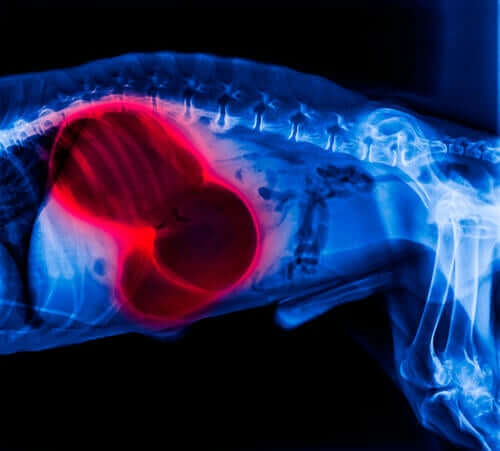

A correta determinação da doença geralmente ocorre quando ela já está altamente desenvolvida, o que dificulta o tratamento do animal. Exames de urina, sangue e fezes, assim como radiografias abdominais após ingestão de substâncias de contraste e ultrassonografia para detectar inflamações fazem parte do protocolo de identificação. Em casos de disseminação para outros órgãos, uma endoscopia também pode ser necessária.